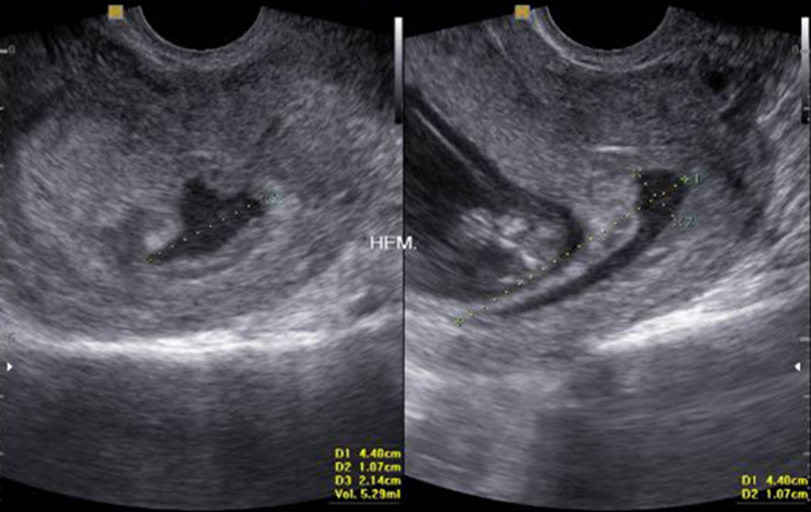

Profile of Patients with Placental Abruption in Ultrasonography

Nickolas Yugo Miyamura Namiuchi, João Italo Fortaleza de Melo, Luiz Dias Dutra, Raphael Oliveira Ramos Franco Netto, Victor Augusto Ramos Fernandes, Rebecca Corrêa Manfredini, Messias Villa Mendonça, Fabio Rocha, Juliana de Almeida Rodrigues Franco Netto, Kayque Wellek Delgado do Amaral, Gabriela Kamiji Baggio Namiuchi

International Journal of Innovative Research in Medical Science·September 1, 2020